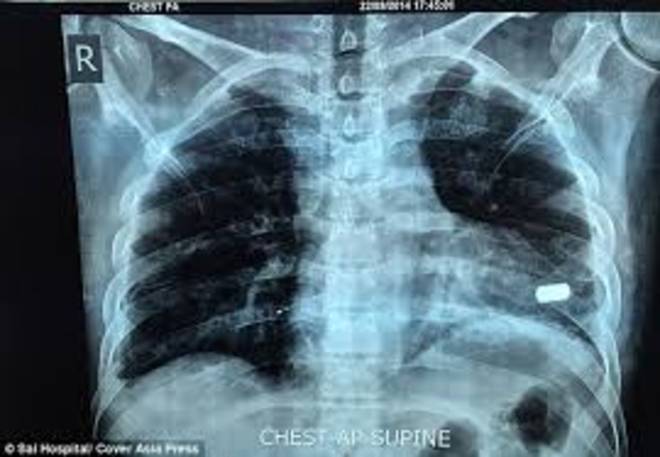

ROMA – Bharat Sharma è un indiano che vive nella regione dell’Uttar Pradesh. L’uomo, 32 anni, si è trovato coinvolto in una rapina mentre era in banca. Sharma, impiegato in un’azienda locale, nel momento della rapina stava depositando assegni per conto dell’ufficio ed è stato colpito da due proiettili calibro 20 sparati dai rapinatori: uno di questi colpi gli si è conficcato proprio nel cuore.

I medici dell’ospedale locale hanno rimosso l’altro proiettile e si sono rifiutati di toccare il cuore dell’uomo per paura che l’operazione gli sarebbe stata fatale. Bharat Sharma ha così dovuto girare per due mesi prima di trovare un ospedale che si prendesse la responsabilità di operarlo per rimuovere l’altro proiettile.

Gli ospedali si rifiutavano di operarlo anche perché l’uomo stava per sposarsi. Tutti avevano paura di compiere un’operazione che si sarebbe potuta rivelare fatale. All0 stesso tempo però, il ragazzo ha rischiato di morire in ogni momento.

Una volta trovato l’ospedale, ‘operazione è durata tre ore e il proiettile, hanno fatto sapere i medici, era a solo un millimetro dal punto in cui avrebbe potuto uccidere Sharma. L’uomo ha ora ha deciso di conservare il proiettile per ricordarsi che per mesi è stato a solo un millimetro dalla morte.